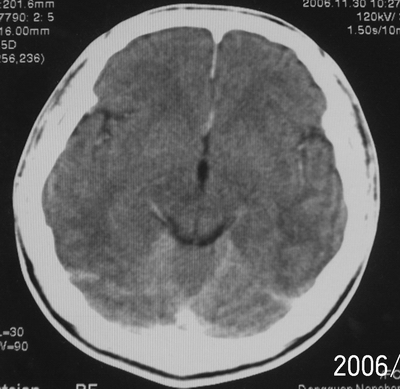

患者、男、18y,头痛5天入院。

左小脑、右丘脑区低密度影,无明显强化及占位表现,男18y,先考虑脑部炎性病变,如脑炎、血行播散性感染等,建议结合临床如脑脊液检验。

单独看左侧小脑半球的不规则形囊性低密度灶,从发病部位、年龄以及无强化、无占位效应的特点可以考虑毛细胞瘤型星形细胞瘤。同样,如果单独看右侧丘脑的近圆形低密度,也可以考虑囊变形星形细胞瘤。只是胶质细胞瘤一般为单发直接浸润、蔓延生长,而不是在脑内同时出现多个病灶,且瘤周没有一点儿水肿,暂时不予以考虑。

左侧小脑半球及右丘脑低密度影,考虑  1、脑梗塞灶. 2、占位性病变,建议作mri检查

左侧小脑半球及右丘脑低密度影,还是在做个mri较为妥当。